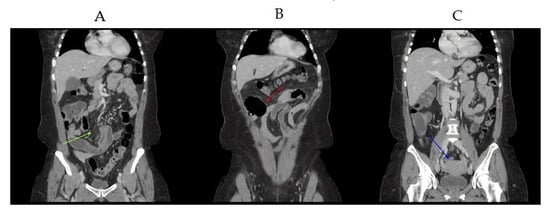

2. Case Study